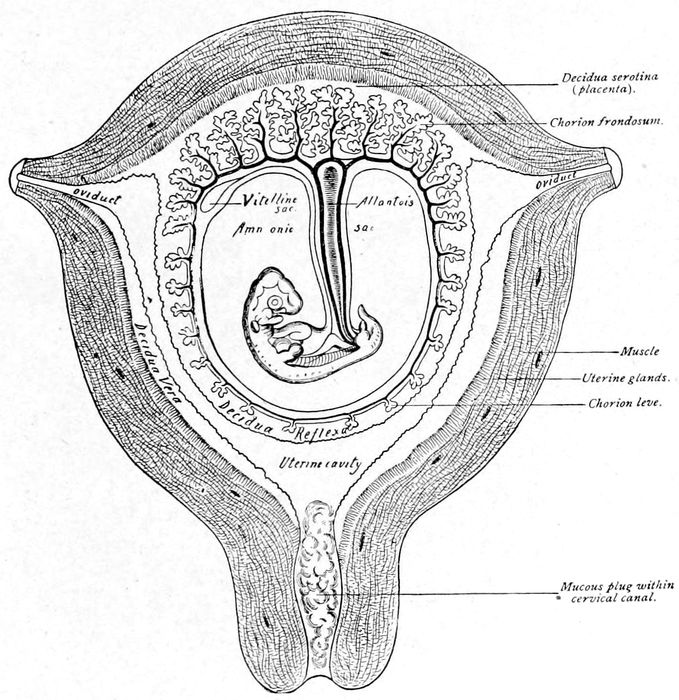

Diagram illustrating relations of structures of the human uterus at the end of the seventh week of pregnancy |

Fig. 16.—Diagram illustrating relations of structures of the human uterus at the end of the seventh week of pregnancy. (American Text Book.)